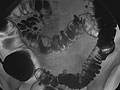

El enema de bario es una radiografía del intestino grueso (colon y recto). También se conoce como examen del tubo digestivo inferior. Esta prueba se utiliza para ayudar a detectar enfermedades y otros problemas que afectan al intestino grueso. Para hacer visible el intestino en una imagen radiográfica, el colon se llena con un material de contraste que contiene bario. Esto se hace vertiendo el material de contraste a través de un tubo que se introduce en el ano. El bario bloquea los rayos X. Esto hace que el colon lleno de bario se vea con claridad en la imagen radiográfica.

• En un estudio de contraste simple, el colon se llena de bario. Esto resalta el intestino y revela anomalías importantes.

• En un estudio de doble contraste o de contraste con aire, primero se llena el colon de bario y a continuación se drena el bario. Esto deja solo una capa delgada de bario en la pared del colon. El colon entonces se llena con aire. Esto proporciona una visión detallada de la superficie interior del colon. Hace que sea más fácil ver zonas estrechadas (compresiones), divertículos e hinchazón.

• Si se realiza un estudio de doble contraste, se drenará el bario y se llenará el colon con aire.

El enema de bario, o examen del tubo digestivo inferior, es una radiografía del intestino grueso (colon y recto).

Se detectan uno o varios problemas en el colon, tales como:

• Una sección del colon que no se llenó de bario.

• Un estrechamiento (compresión) en el intestino.

• Pólipos o crecimientos en la pared interior del colon.

• Sacos en la pared del colon ( diverticulosis).

• Problemas con anomalías e inflamación (colitis) del revestimiento del colon.

• Un segmento estrechado o un asa intestinal retorcida que está causando una obstrucción.

• Un intestino plegado en un niño, lo que es señal de invaginación. El enema de bario puede usarse como tratamiento para que el intestino vuelva a su posición normal.